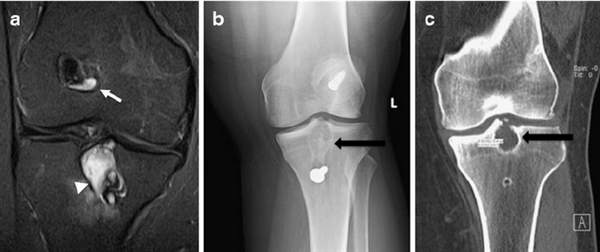

Хондробластома. В 1931 году Codman подробно описал это новообразование костей под названием «эпифизарная хондроматозная гигантоклеточная опухоль». В литературе можно встретить описание ее под названием опухоли Кодмена. В 1942 году Jaffe и Lichtenstein выделили эту опухоль в самостоятельную форму под названием «хондробластома», состоящую в основном из хондробластов.

Хондробластома — это редкая опухоль. Судя по данным литературы, она составляет 1—1,8% среди первичных опухолей костей. Болеют лица обоего поля, но чаще мужского. Хондробластома встречается в любом возрасте, но преимущественно, в детском и юношеском (10—25 лет). Излюбленная локализация — длинные трубчатые кости. Реже хондробластома расположена в лопатке, ребре, пяточной кости, костях кисти и стопы. В длинных трубчатых костях ходробластома поражает эпифиз и метафиз (проксимальный и дистальный отделы бедренной кости, проксимальный — большеберцовой и плечевой кости, проксимальный отдел лучевой кости). Хондробластома распространяется в сторону сустава, и в ряде случаев отмечается реактивный выпот в суставе. Патологические переломы наблюдаются редко.

Рентгенологическая картина имеет ряд особенностей. Определяется очаг деструкции округлой или овальной формы. Он не однороден. Вследствие наличия в опухоли участков обызвествления, на рентгенограмме видны крапчатые тени. При субкортикальном расположении очага возможна небольшая периостальная реакция. Кортикальный слой может быть истончен, иногда целостность его нарушается и опухоль выходит за пределы кости, что не является, как и при остеобластокластоме, признаком ее малигнизации.

Дифференциальный диагноз хондробластомы проводится со многими опухолями костей и прежде всего с солитарной хондромой. Сложна диагностика хондробластомы и туберкулезного остита. При потере активности туберкулезный очаг окружен склеротической каймой, что может имитировать хондробластому. При артритической фазе туберкулезного остита боль и выпот в суставе выражены резче. На рентгенограммах определяется изменение высоты суставной щели, утолщение суставной сумки, общий остеопороз костей, что не характерно для хондробластомы. Стихание клинических проявлений при туберкулезном остите после применения специфического лечения, специфические реакции и лабораторные данные разрешают сомнения в диагнозе. Лечение хондробластомы осуществляется хирургическим методом. Прогноз для жизни, как правило, благоприятный.